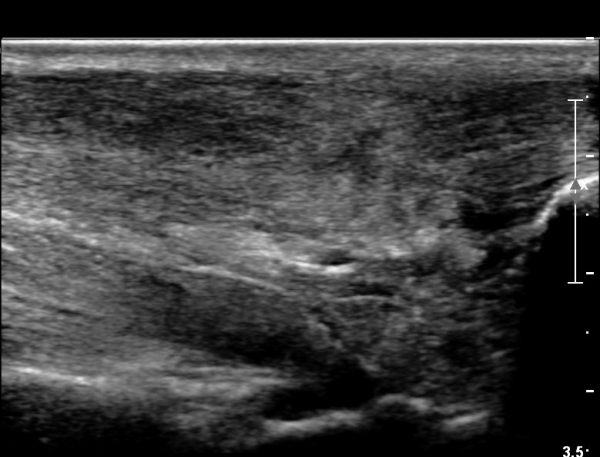

¾ÆÅ³·¹½º°Ç Á¾´Ü¸é°Ë»ç¿¡¼­ ¾ÆÅ³·¹½º°Ç ¸»´ÜºÎ¿¡ ¾ÆÅ³·¹½º°ÇÀÇ Àú¿¡ÄÚºÎÁ¾, ±¹¼ÒÀû ¿¬°á¼º ¼Ò½Ç,

¹ß¸ñ°üÀý ÈĹæºÎ¿¡ ¼ö¾×Àú·ù°¡ °üÂûµÊ(»çÁø 3, 4, 5).